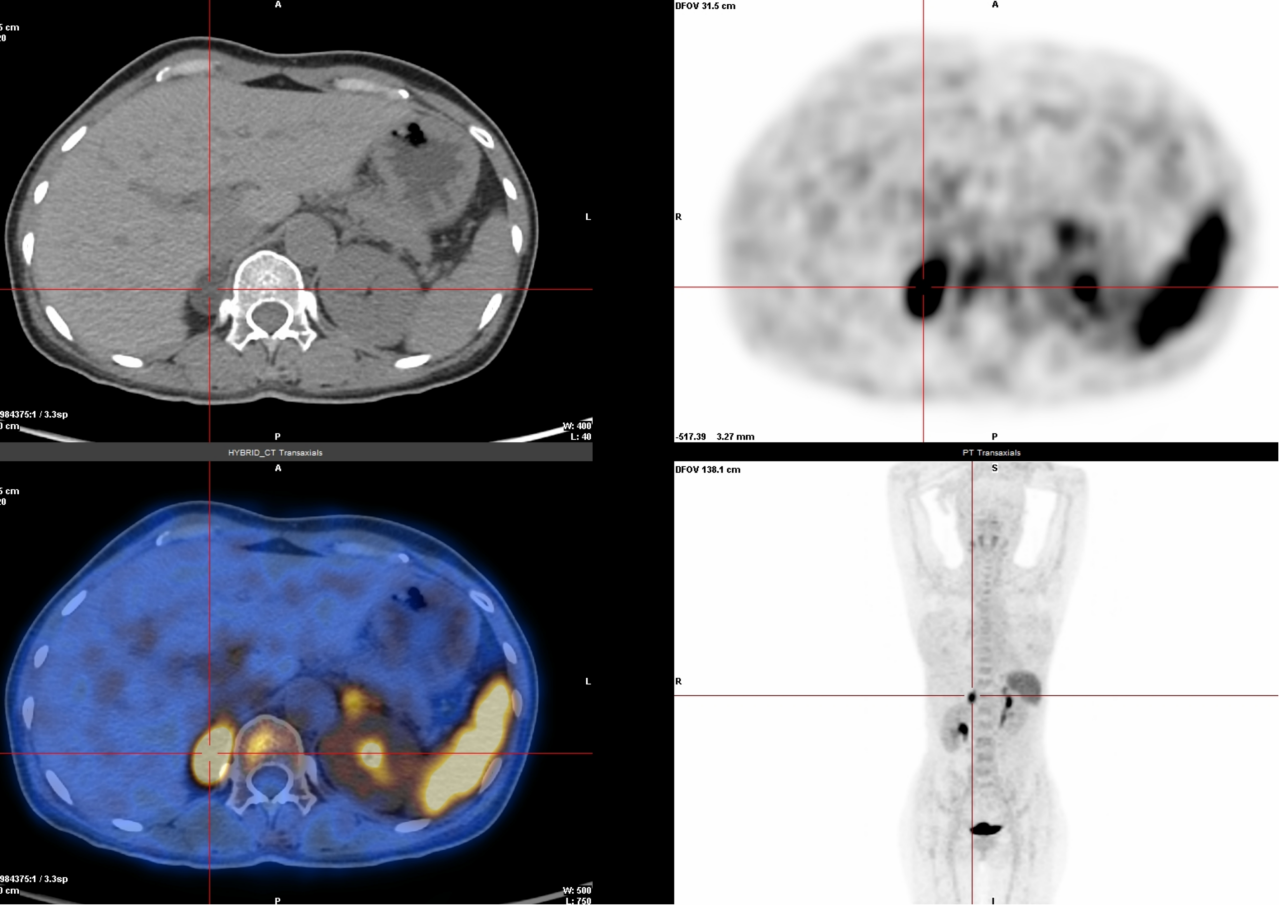

5. 胰岛细胞瘤检查(68Ga-Exendin4):专门用于找胰岛细胞瘤(一种胰腺肿瘤),准确率极高,几乎不会误诊或漏诊。

△胰头钩突部胰岛细胞瘤